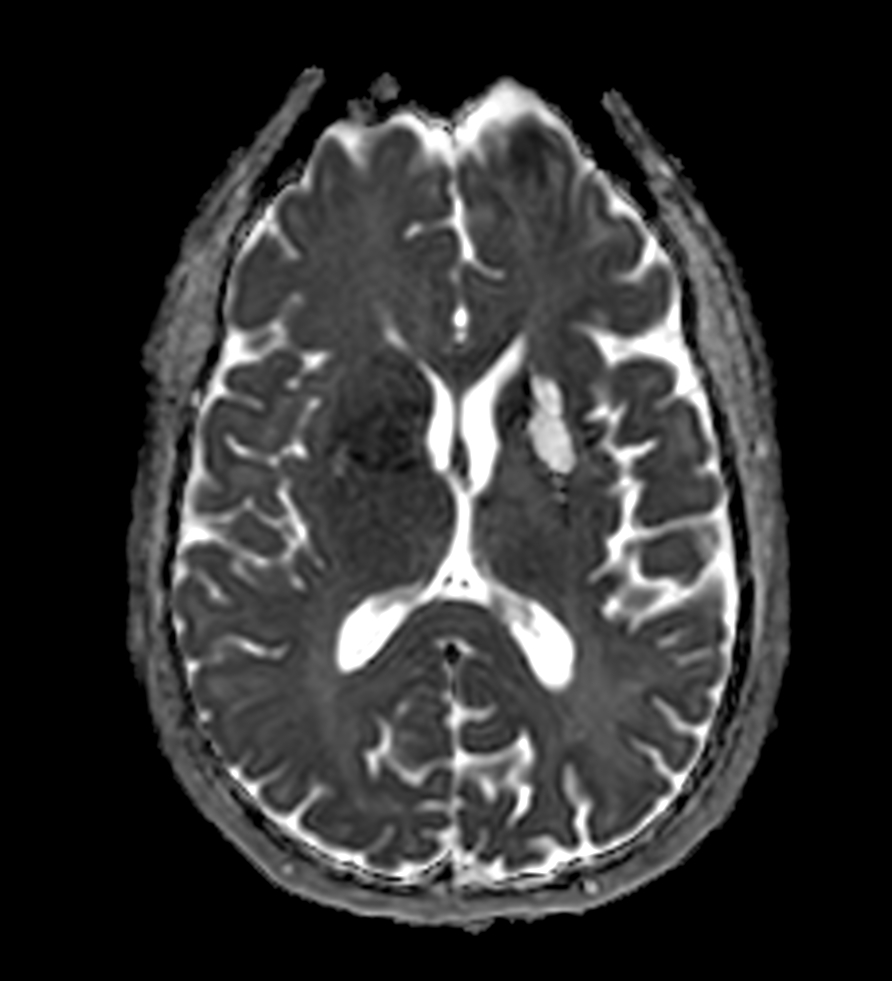

3D VIEW - T2w FLAIR

-